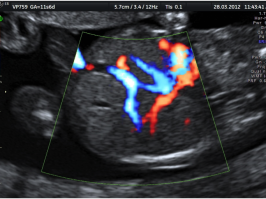

Cuore; 4 Camere

Cuore; Arteria Polmonare

Cuore; Emergenza Aortica; Setto Interventricolare

Arco Aortico e vasi brachio cefalici